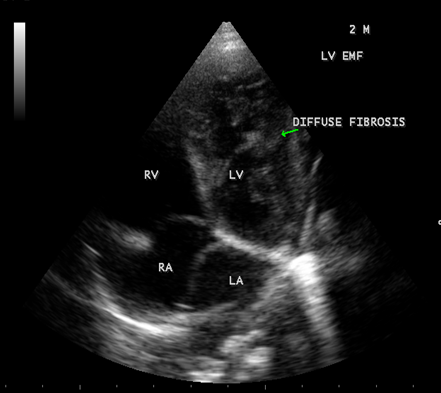

Case 6. Left ventricular endomyocardial fibrosis mimicking as Apical left ventricular hypertrophic cardiomyopathy in a 2- year old male child as shown in Figures 23 , 24 and 25.

Figure 23: (Left ventricular endomyocardial fibrosis mimicking as apical left ventricular hypertrophic cardiomyopathy in a 2- year old male child}

Figure 24: Apical four chamber view showing the endocardial fibrosis of the left ventricle in a 2-year old male child

Figure 25 Apical four chamber view showing diffuse endocardial fibrosis of left ventricle in 2-year old male child.

A left ventricular EMF mimicking apical left ventricular hypertrophic cardiomyopathy in a year-old boy as shown in Figures 23, 24 and 25 in a 2-year old male child and an apical right ventricular cardiomyopathy in a year-old female as shown in Figure 26 mimicking as right ventricular EMF have been found by Transthoracic echocardiographic screening. A right ventricular EMF associated with Psoriasis as shown in Figure 3 to7 in a 52- year old male and a left ventricular EMF associated with pemphigus in a 63- year old male as in Figure 39 were detected in this region of Thoothukudi.